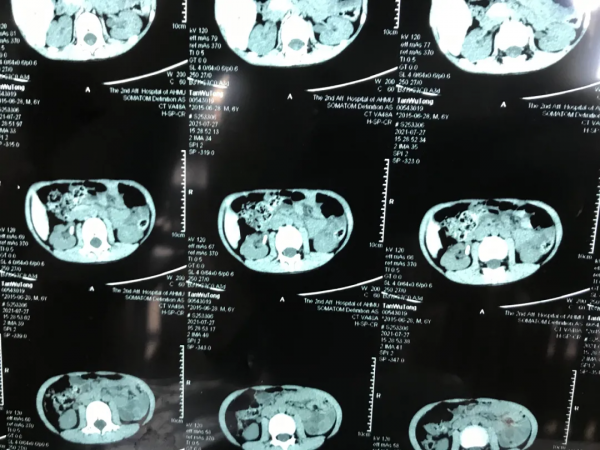

現病史:因“腹痛兩天”入院,CT檢查發現右腎盂出口1.4x1.0cm結石,經完善檢查,擬行F4.8針式腎鏡PCNL碎石術

結合術前CT,規劃穿刺通路:此次病例結石是一個單純的腎盂結石,理論上腎上中下盞入路均可以穿刺碎石。但因F4.8針式腎鏡鏡體的剛性不足,不能過度的撬撥。結合術中B超影像,術者選擇了一個背側的中盞入路。穿刺點位於十一肋間。